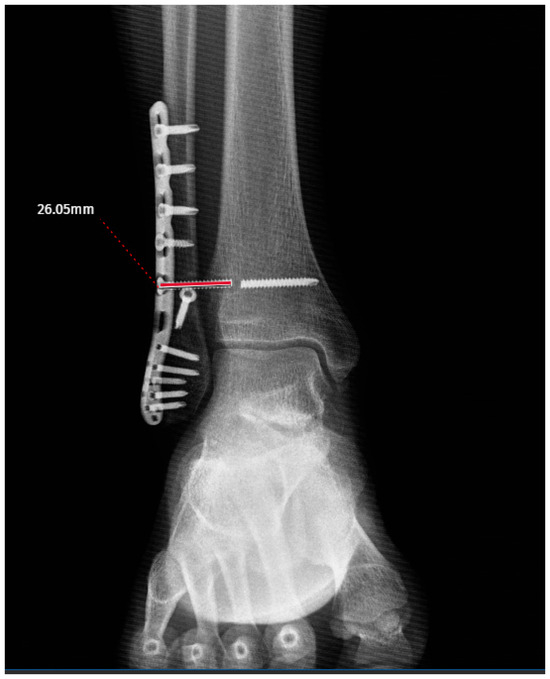

Radiographic and Demographic Factors Associated with Syndesmotic Screw Breakage in Ankle Fractures

by Emre Kocazeybek, Mehmet Ekinci, Salih Magi, Murat Altunsoy, Kubilay Yolaçan, Murat Yılmaz and Mehmet Ersin

J. Clin. Med. 2026, 15(7), 2647; https://doi.org/10.3390/jcm15072647 - 31 Mar 2026

Background: Syndesmotic screw breakage is a well-recognized mechanical complication following ankle fracture fixation. Although several studies have investigated patient-related and technical factors associated with screw breakage, the temporal pattern of screw failure and implant survival remains less clearly defined. Therefore, this study aimed [...] Read more.

Background: Syndesmotic screw breakage is a well-recognized mechanical complication following ankle fracture fixation. Although several studies have investigated patient-related and technical factors associated with screw breakage, the temporal pattern of screw failure and implant survival remains less clearly defined. Therefore, this study aimed to evaluate one-year syndesmotic screw survival using time-to-event analysis and to identify factors associated with screw breakage. Materials and Methods: A total of 132 patients with unstable AO-Weber 44-B/C ankle fractures treated with syndesmotic screw fixation were retrospectively analyzed. Patients were followed for a minimum of 12 months or until screw breakage occurred. Screw survival was evaluated using Kaplan–Meier analysis and Cox proportional hazards regression was performed to identify factors associated with screw breakage. Demographic variables, fracture type, and screw-related parameters were analyzed. Receiver operating characteristic (ROC) analysis was used to assess the discriminative ability of age. Results: Screw breakage occurred in 31 patients (23.5%) during follow-up. Kaplan–Meier analysis demonstrated significantly lower screw survival in Weber C fractures compared with Weber B fractures (log-rank p < 0.001). Cox regression analysis identified younger age (HR: 0.965, 95% CI: 0.937–0.993, p = 0.016) and Weber C fracture type (HR: 1.811, 95% CI: 1.260–2.602, p = 0.001) as independent predictors of screw breakage. ROC analysis showed that age had moderate discriminative ability (AUC: 0.719, 95% CI: 0.612–0.816), with a cut-off value of 35.5 years. Conclusions: Younger age and Weber C fracture type are associated with an increased risk of syndesmotic screw breakage and Weber C fractures also demonstrating reduced screw survival. These findings may assist in patient counseling; however, the clinical implications of screw breakage remain uncertain. Full article